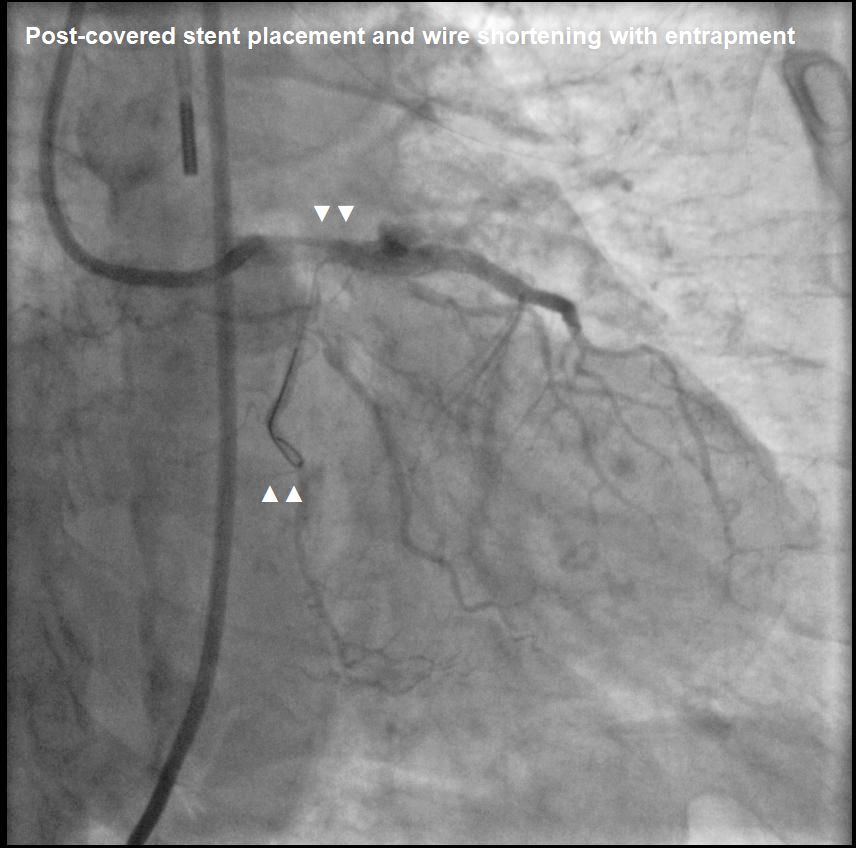

Wire entrapment from LCx to LAD-LM.Median sternotomy, CPB established. LV venting via RSPV & PA. Cardioplegia via root. Aortocoronary bypass to mid-LAD with vein graft. V-A ECMO post-CPB.

Wire entrapment from LCx to LAD-LM.Median sternotomy, CPB established. LV venting via RSPV & PA. Cardioplegia via root. Aortocoronary bypass to mid-LAD with vein graft. V-A ECMO post-CPB.

Aorta incised, wire cut near LMCA ostium.

Aortorrhaphy with 5-0 Prolene. CPB weaned, wound closed.

Guidewire entrapment during PCI is rare. In this case, the complication began with stent malapposition in the LAD, followed by post-dilatation that led to vessel perforation. During prolonged balloon inflation, the LCx wire was inadvertently pulled into the LAD, leading to guidewire entrapment when a covered stent was placed. Direct retrieval using a microcatheter was not possible, requiring surgery to cut the guidewire at the LM ostium, with the remaining LCx wire covered by a stent.